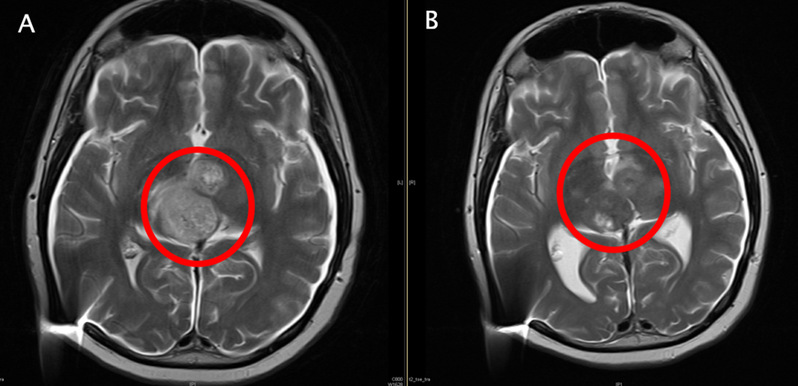

新南威尔士大学儿童癌症中心的David Ziegler团队在SNO会议中以讲座报告介绍了ACT001治疗儿童弥漫性内生性脑桥胶质瘤(DIPG)的临床试验结果(https://app.oxfordabstracts.com/events/1809/program-app/submission/233921)。DIPG属于儿童脑干肿瘤,手术无法切除,没有获批的标准治疗药物,中位生存期不到1年,长期生存率不足1%,是最难治的恶性肿瘤之一。SNO会议报道了通过超高剂量的ACT001治疗,多位DIPG患儿身上出现良好的临床反应,其中一位患者的肿瘤细胞密度大幅降低,临床症状评分(KPS评分)从50提升到90(见下图,A为基线MRI)。